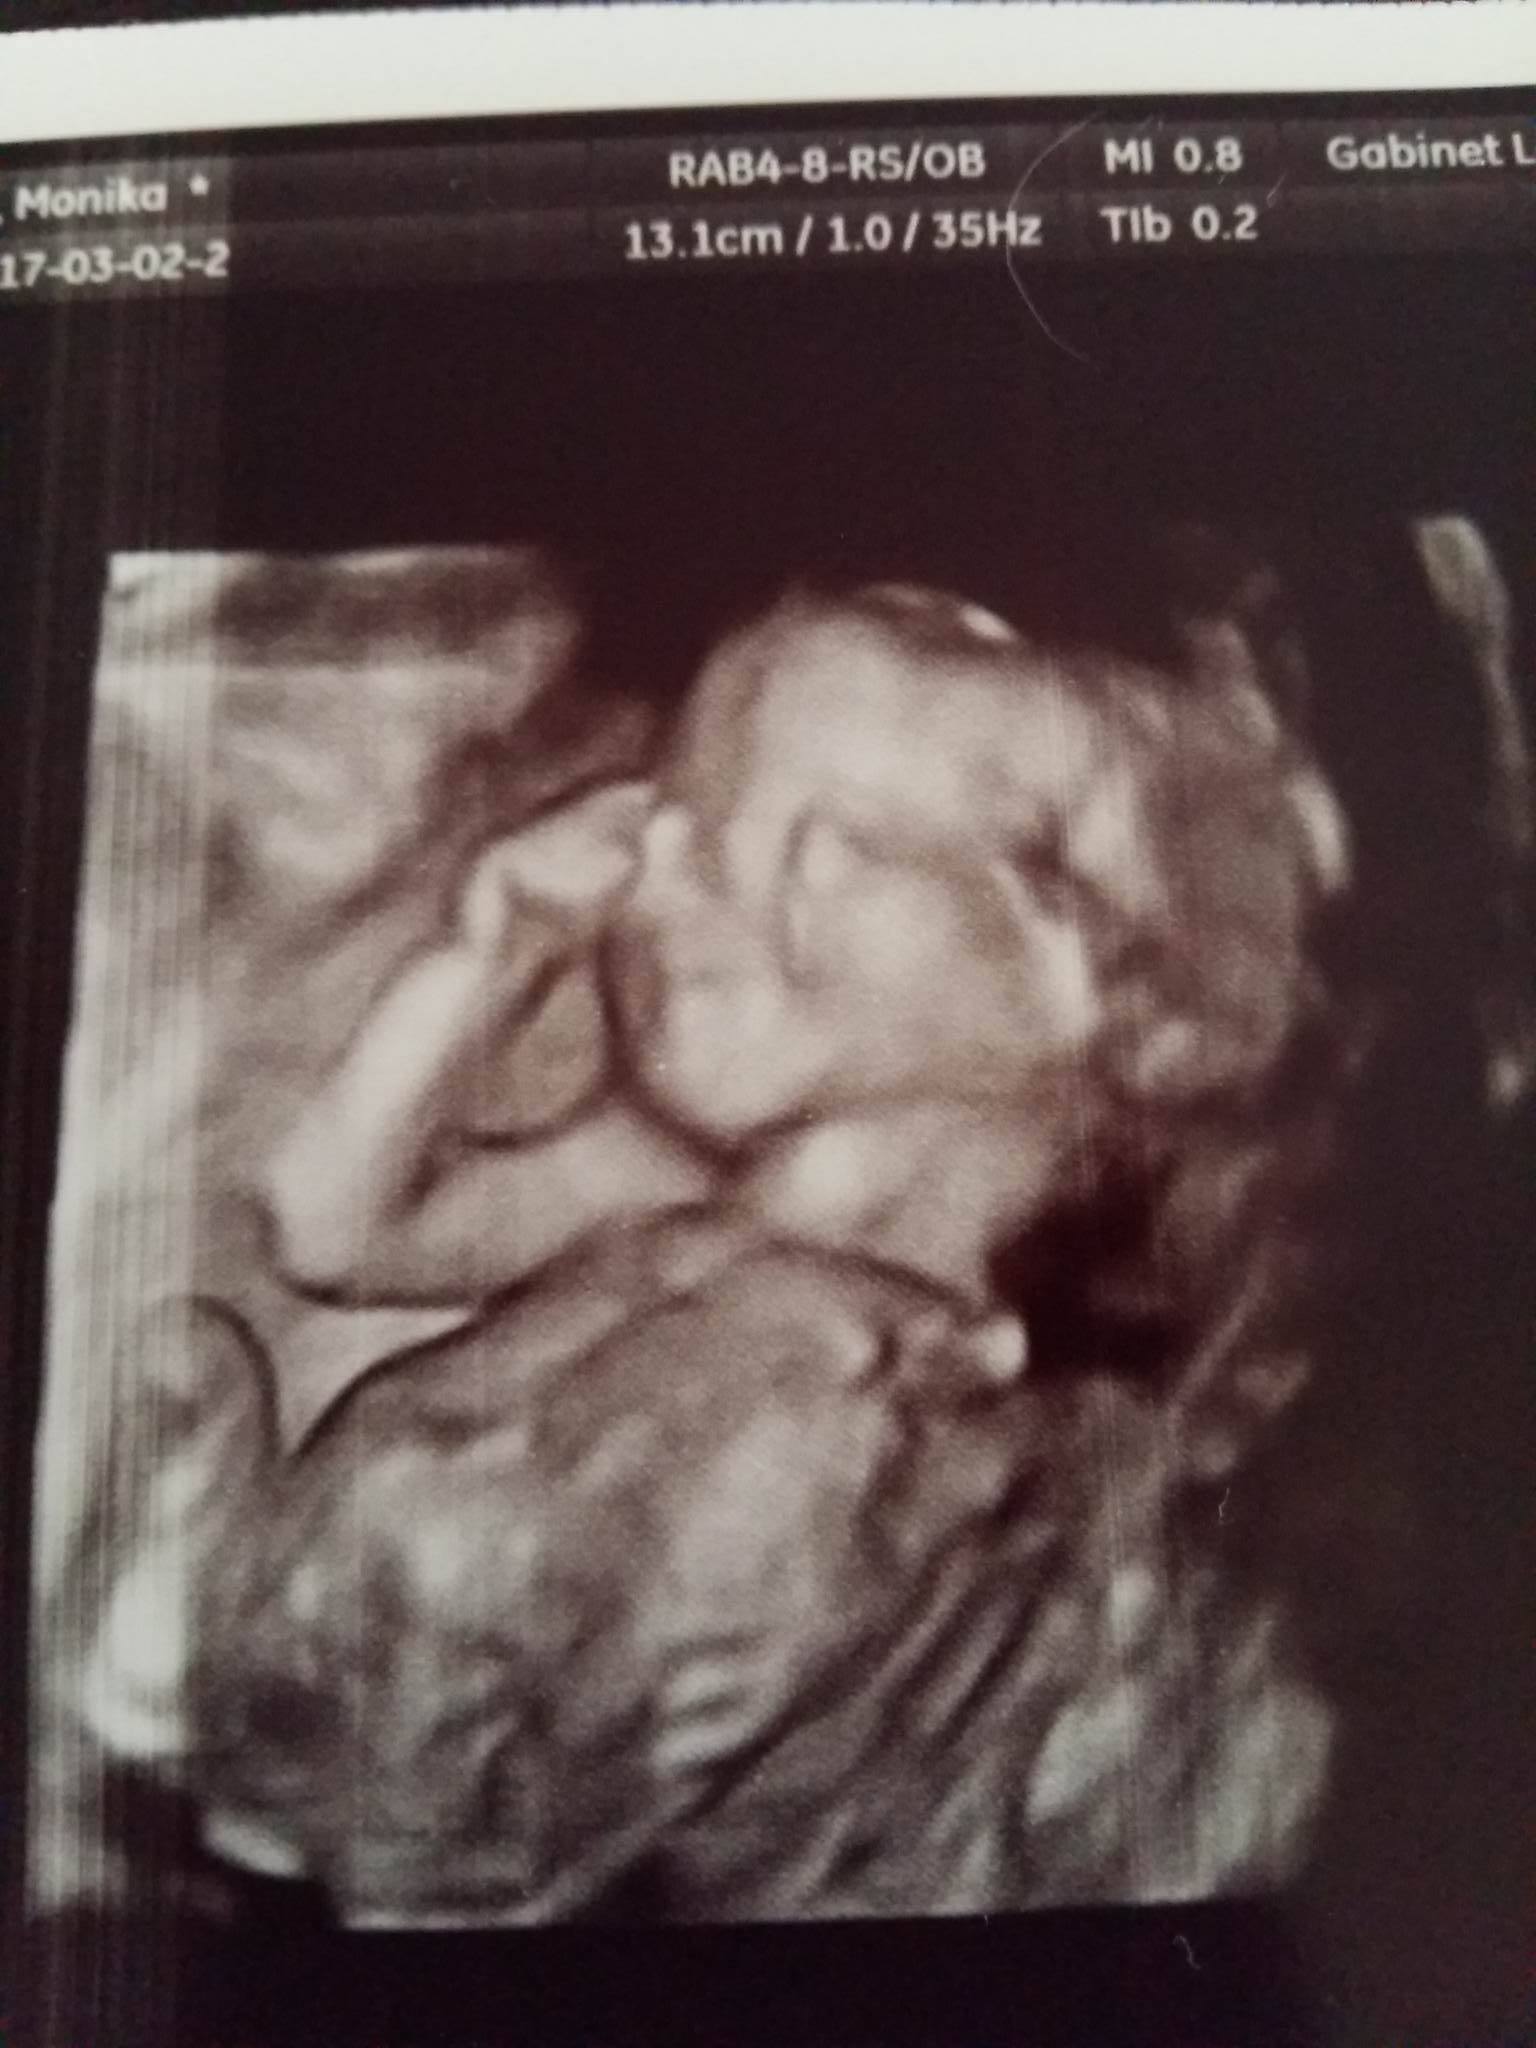

W pierwszej ciąży to pamiętam że już synek szalał a tu cichutko siedzi.. Płacę 180 zł jak za zwykłą wizytę, a na każdej mam 3d i muszę Wam pokazać jak pięknie zapozował ostatnio

Zobacz załącznik 807378 zobaczcie jak się uśmiecha <3